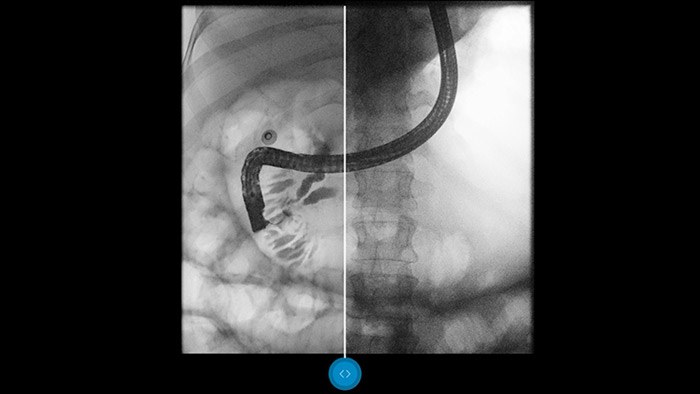

Vergleichen Sie Dynamic UNIQUE mit einer klassischen Bildverarbeitung und lassen Sie sich überzeugen.

Bei den heutigen Durchleuchtungsuntersuchungen sind Niedrigdosis-Einstellungen durchaus üblich. Leider führt dies zu Bildern mit hoher Quantenstreuung, durch die Ihnen eine sichere Diagnose erschwert wird. Die Echtzeit-Bildverarbeitung von Dynamic UNIQUE (Unified Image Quality) ist ein Innovationsvorsprung, von dem Sie nur bei Radiographie-/Fluoroskopiesystemen von Philips, einschliesslich dem ProxiDiagnost N90 und dem CombiDiagnost R90, profitieren können. Mit Dynamic UNIQUE optimieren Sie Ihre Bildgebungsergebnisse und somit Ihre Diagnosesicherheit.

Dynamic UNIQUE liefert hervorragende Detailerkennbarkeit mit Echtzeit-Rauschunterdrückung – vom ersten bis zum letzten Bildbereich. Diagnostische Informationen werden für jeden Bildbereich mit grosser Klarheit, der richtigen Helligkeit und äusserst niedriger Latenz angezeigt. Die Bilddarstellung ist einheitlich und stabil, selbst wenn sich der Bildinhalt schnell verändert. Dynamic UNIQUE bietet durch seine Detailschärfe schnelle und sichere Niedrigdosis-Untersuchungen, um Ihre Diagnosesicherheit zu steigern.